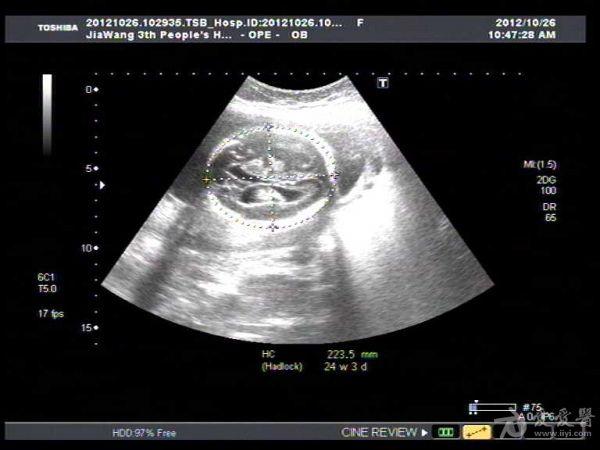

此孕妇22岁,于孕六月来我院产检,可见胎儿侧脑室扩张积液约1.4Cm,遂告知小孩脑

积水,此孕妇接着去我们当地三甲医院检查,也被告知胎儿脑积水,建议引产。

此孕妇听信家人说吃核桃能补脑,吃了两个月核桃来来复查,脑积水更明显。